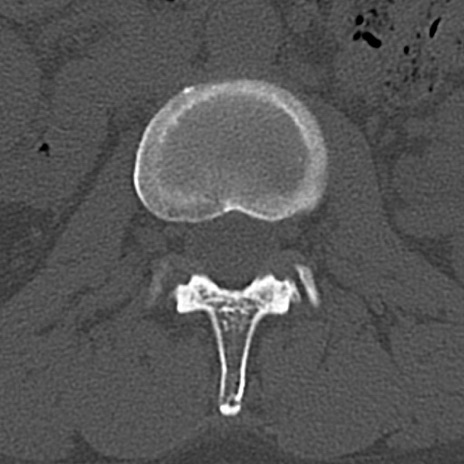

【整形】TIPS症例4 腰椎CT(横断像)

腰椎CT

横断像と矢状断像